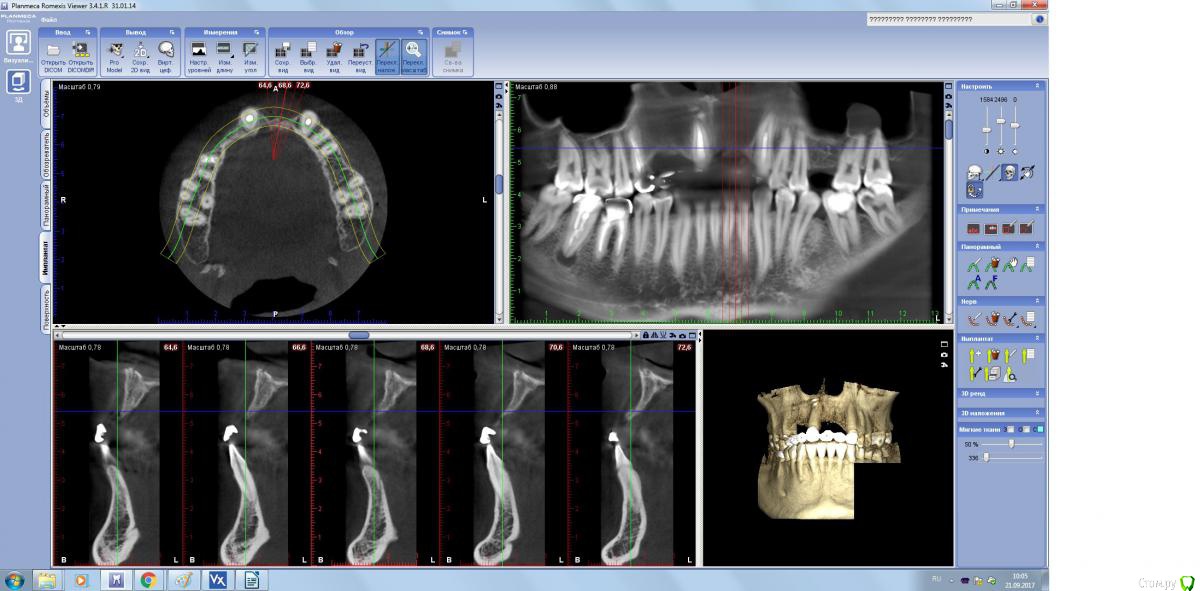

Пришел парнишка на имплантацию, но как видите ряд проблем присутствуют.

1. Можно ли восстановить сначала один сегмент а потом второй сегмент, почему спрашиваю, если идти двух этапно, какой дизайн разреза должен быть во второй раз и как мобилизоваться?

2.Надо ли перекрывать ССТ?

3. Можно ли пока оставить зубы? они конечно негодные, но хоть как то помогут мне в пластике...

1ый сегмент не очень удобен для фиксации пластины. Проще будет сосидж и перекрыть Вип ст. Зубы (11,23)лучше оставить. А какой дизайн разреза будет в первый раз?

Не верю я особо в сосидж то во фронте, в цитопласт верю, но его не успеют привезти.. а дизайн разреза стандартная трапеция.